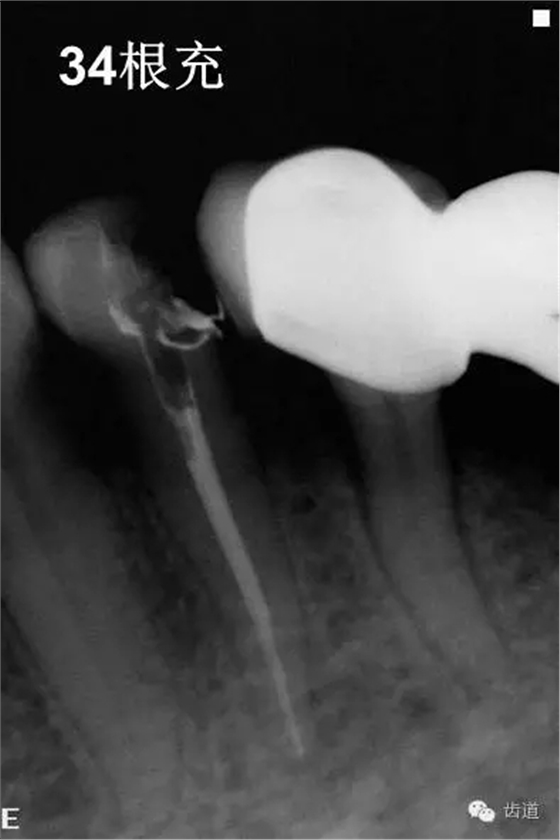

4、34常規(guī)根管治療。(2013年8月)

3、34術(shù)前片顯示遠中面暗影近髓